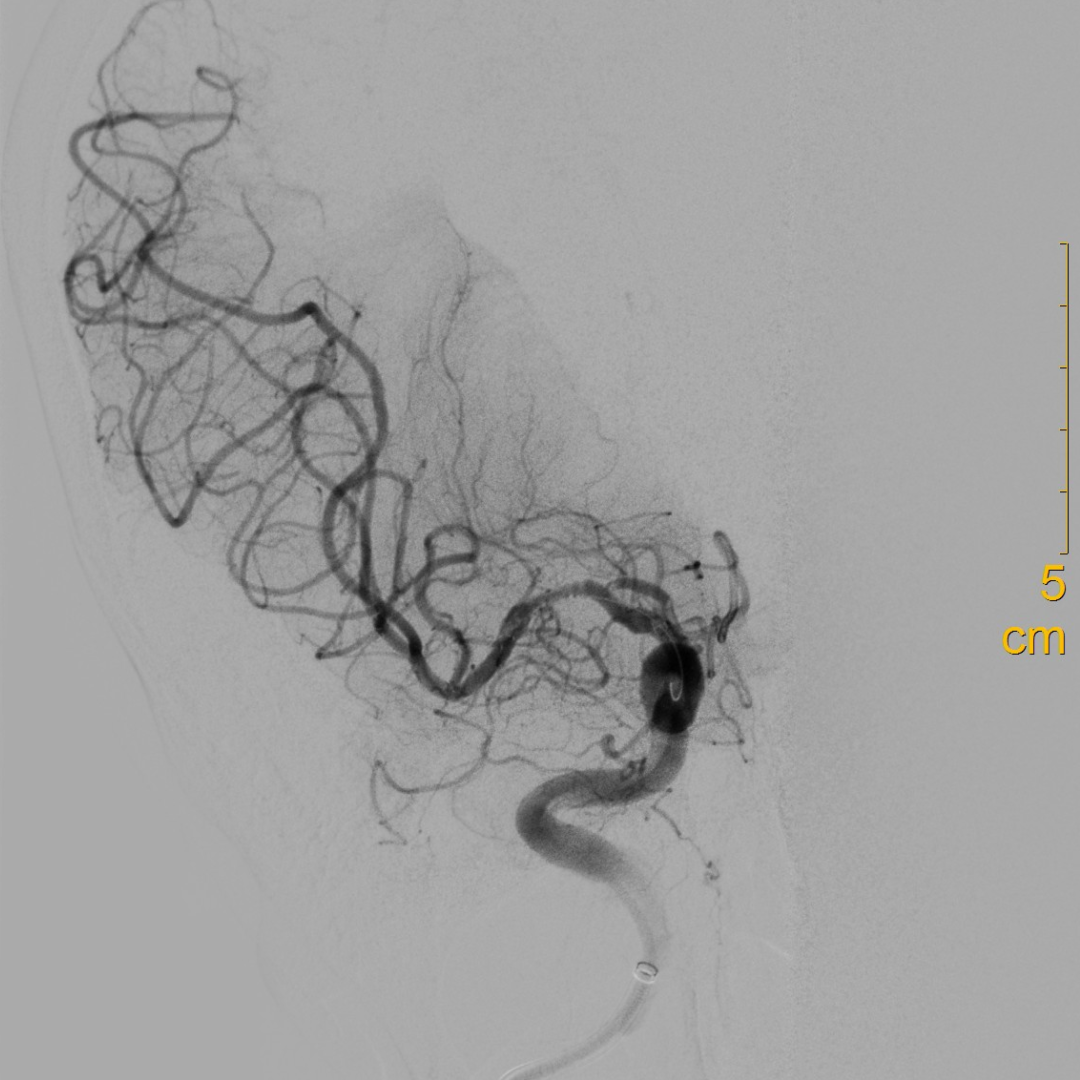

造影可见闭塞残端细小,结合多时相CT,考虑倾向于狭窄性病变。

什么叫桡鞘【例久弥新】寻道于桡——瑞康通5.5F IntroSky X导管鞘经桡动脉行右侧大脑中动脉取栓一例_https://www.jmylbn.com_新闻资讯_第14张

释放支架后造影。

扩张后造影见血流改善,支架内未见明显血栓影。

观察10分钟回收支架后,继续观察15分钟提示血流良好。

从完成穿刺到血管开通总用时仅40分钟。